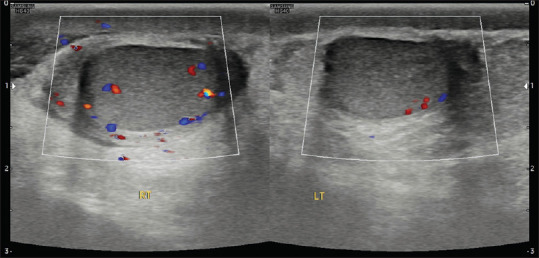

Acute Scrotal Pain - Role of Sonographic Evaluation in Solving Diagnostic Dilemma.